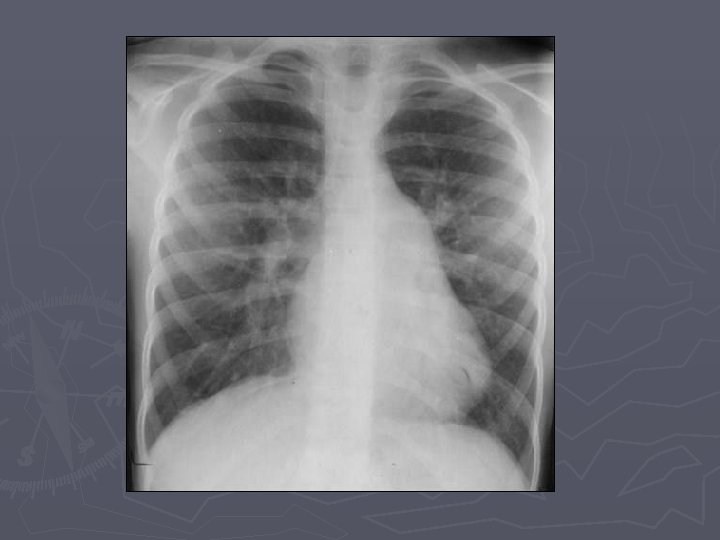

Findings ► XR – small to moderate defects have normal radiographs ► XR - large defects have cardiomegaly with the main PA normal or enlarged, with shunt vascularity, later on PA and RV enlarge ► CTA – defect in atrial septum, enlargement of RA, RV and PA ► MR – can quantify shunt volume on volumetric cine MR or velocity encoded cine MR

Differential diagnoses ► Normal chest ► VSD ► Pulmonary HTN ► Scimitar syndrome (Anomalous connection of the right pulmonary veins to the inferior vena cava results in a chest radiographic shadow that resembles a Turkish sword, hence the designation scimitar syndrome)

► Frontal chest radiograph in adult patient with the same entity (image 3) shows moderate to severe cardiomegaly with enlarged central pulmonary arteries and peripheral tapering of pulmonary vessels.